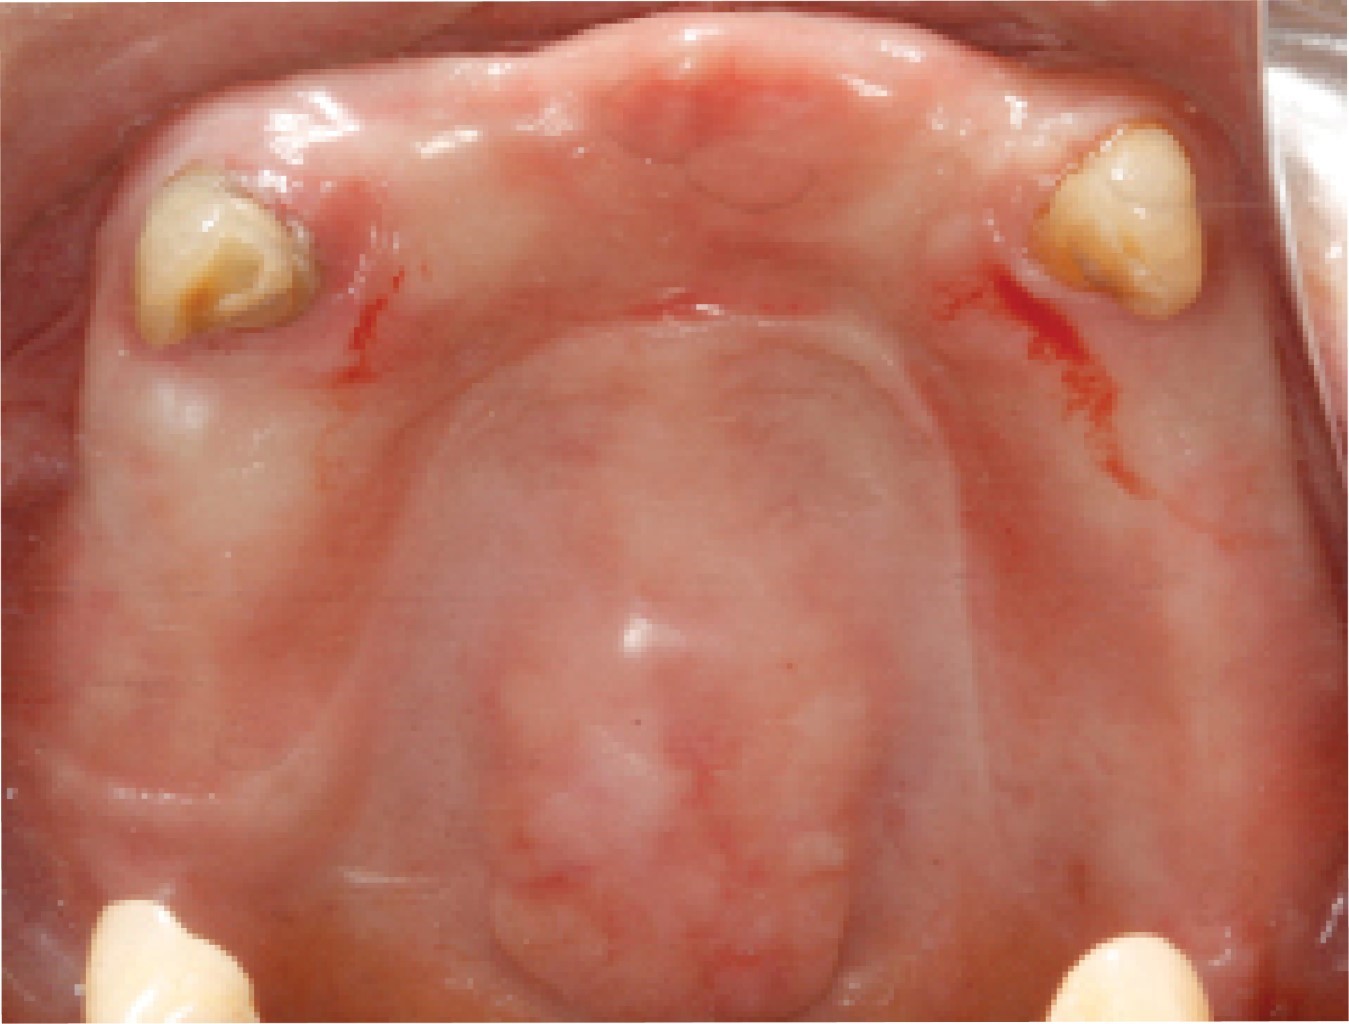

Hoy en día el uso de implantes dentales constituye el estándar de oro en la rehabilitación protésica de pacientes edéntulos. Especialmente en los pacientes totalmente edéntulos, es importante una correcta colocación tridimensional de los implantes para garantizar unos resultados funcionales y estéticos adecuados. En los últimos años, el uso de sistemas quirúrgicos guiados por ordenador ha permitido la colocación de implantes con una precisión casi exacta del resultado quirúrgico/protésico final. El presente caso describe un enfoque sin colgajo para la rehabilitación completa de pacientes edéntulos mediante el protocolo de doble escaneo para la planificación virtual de la colocación de implantes y el diseño de la guía quirúrgica para la rehabilitación de implantes en pacientes totalmente edéntulos. La cirugía guiada es actualmente una alternativa que permite, en los casos adecuados, realizar un abordaje sin colgajo, lo que reduce las molestias del paciente, el tiempo quirúrgico y mejora la precisión de la colocación del implante al reducir el error del operador.

Figura 1